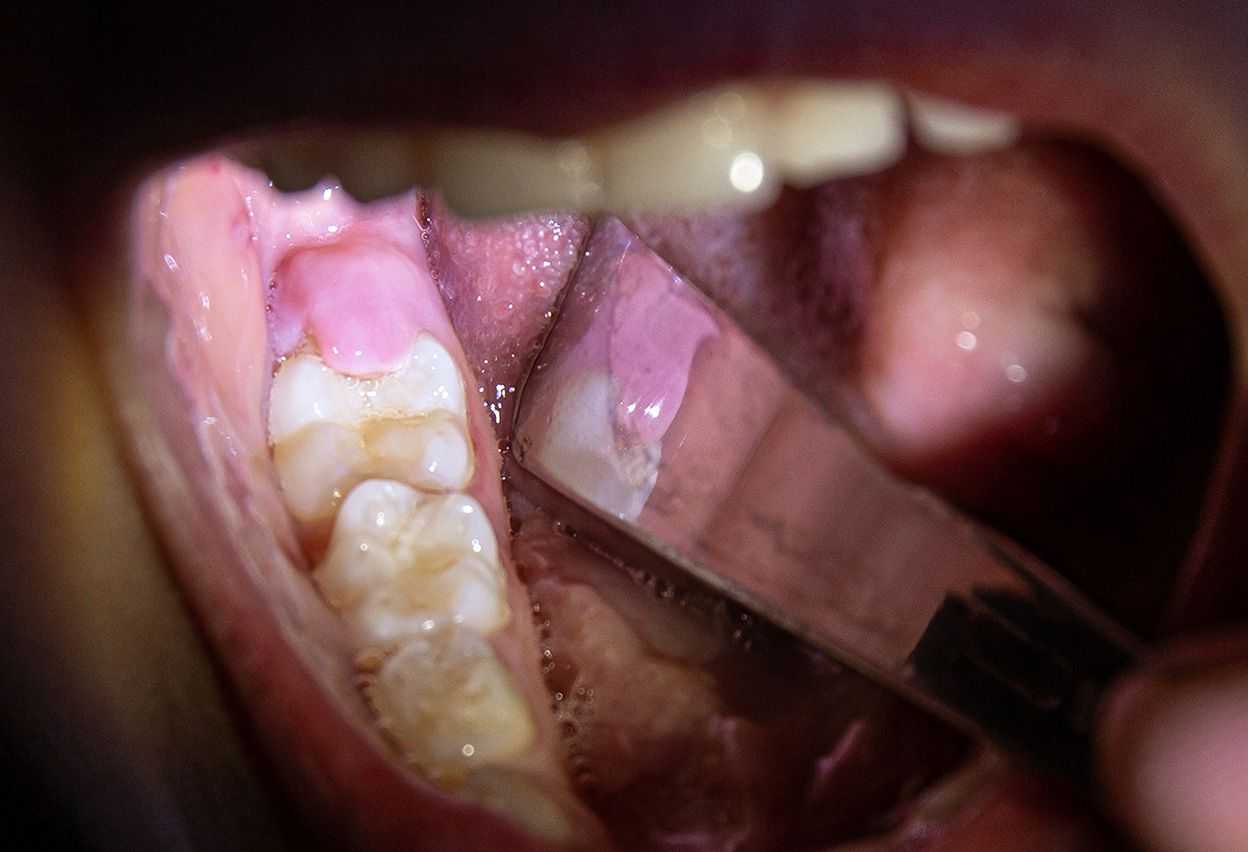

Gum Flap Over Wisdom Tooth? Everything You Need To Know

Have a gum flap over your wisdom tooth? It’s called an “operculum.”